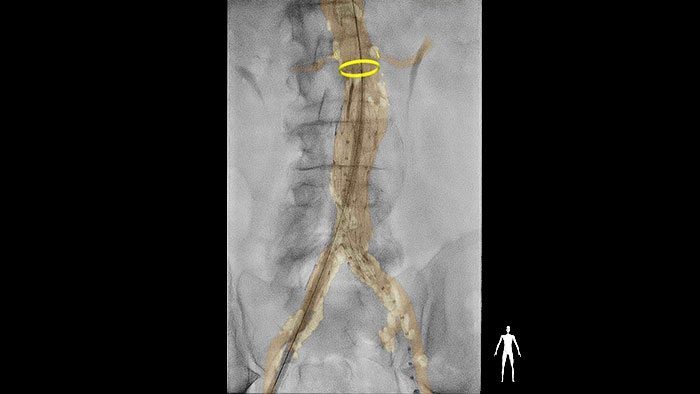

Технологии для исследований сосудов были разработаны для поддержки различных процедур на аорте, периферических артериях и венах. От восстановления проходимости сосуда до лечения аневризмы или окклюзии – наши решения помогают врачам проводить быстрые, эффективные и упрощенные процедуры.

Узнать большеКомплексные решения Philips для интервенционной визуализации, планирования и навигации, которые помогут повысить успешность операций и выполнить анализ результатов лечения пациентов с заболеваниями аорты.